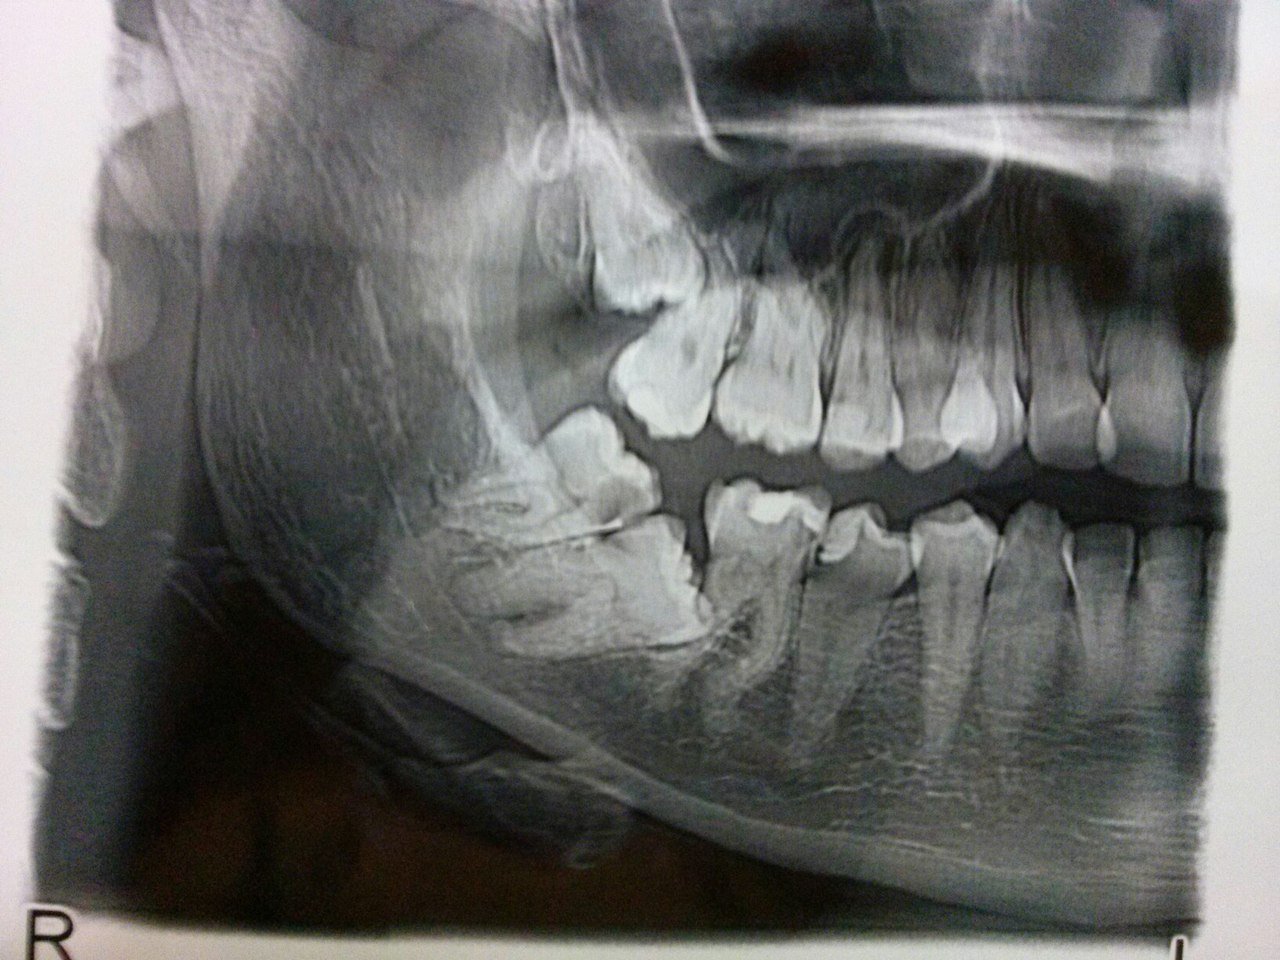

похоже?:

Нажмите на изображение для увеличения

Название: 2015403141102.jpg

Просмотров: 64

Размер:	121.7 Кб

ID:	9898237

и где вы такое берёте?

я, даже, сначала подумал, что это один и тот же пациент.

тактику сочиняли впятером.

в итоге, в данном конкретном случае принято такое решение:

- удаление 6 (уже сделано. было не просто)

- ортодонтическое перемещение 7 на место 6 и 8 на место 7.

а, самое главное чуть не забыл.

причина обращения! жалобы были: глубокий карман в области 6 зуба, запах, то сё... терапевты не справлялись.